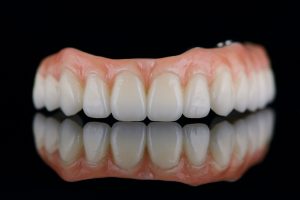

An upper dental implant is a three-part system: the implant (the metal screw in bone), the abutment (connector), and the crown (the visible tooth). Upper implants sit in the maxilla, which has different bone shape and thinner bone than the lower jaw. That affects placement angle and how forces from chewing are distributed.

After healing, an abutment is placed and impressions taken for a custom crown. The crown is adjusted for bite and appearance to match neighbouring teeth.